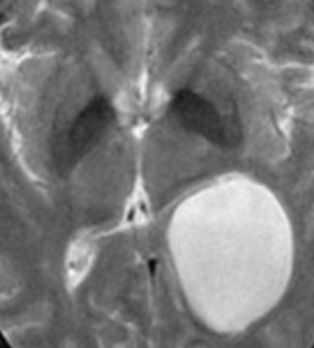

Дермоидные кисты встречаются реже эпидермоидных, составляя около 0,3 % от внутричерепных образований. Обычно выявляются в возрасте между 10 и 20 годами. Морфологически от эпидермоидов их отличает наличие эктодермальных элементов - волосяных фолликулов, потовых желёз и т.д. Типично они расположены по средней линии (в отличие от эпидермоидов, которые чаще внеосевые): в супраселлярной цистерне, субфронтально, вокруг моста и, очень редко парапинеально, периорбитально, в IV желудочке, в области конского хвоста и интрадиплоидно. От эпидермоидных кист на МРТ головного мозга их отличает только выраженная неоднородность структуры, кроме того, они всегда яркие на Т1-зависимых МРТ головного мозга за счёт большого содержания липидов. При разрыве и прорыве в субарахноидальное пространство в нём появляется уровень, на Т1-зависимых МРТ головного мозга светлый жир плавает на ликворе.

![Dermoid rupture]()

МРТ головного мозга. Т1-взвешенная аксиальная МРТ. Прорыв дермоидной кисты в субарахноидальное пространство.